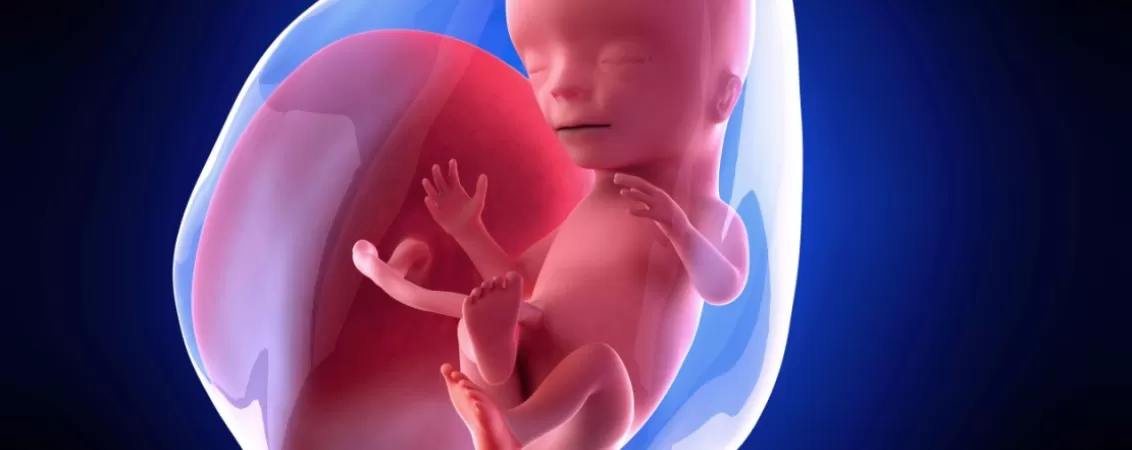

Dacă ești însărcinată în 15 săptămâni, te afli deja în luna a patra de sarcină și ești aproape de jumătatea drumului, adică a mai rămas puțin până când îți vei cunoaște copilul. Această etapă coincide cu schimbări fizice vizibile în cazul majorității femeilor deoarece bebelușul se dezvoltă rapid: cântărește aproximativ 70 de grame (cam cât un măr) și măsoară undeva la 10 cm. Așadar, trebuie să te pregătești pentru o creștere semnificativă a burticii în următoarele săptămâni.

Cu fiecare săptămână care trece, fătul seamănă tot mai mult cu bebelușul care urmează să vină pe lume. Urechile sunt deja poziționate normal, pe părțile laterale ale capului, iar ochii se mișcă spre partea din față, pregătindu-se pentru primul contact vizual cu mama.

În săptămâna 15 de sarcină bebelușii exersează mișcările de respirație, înghițirea, dar și abilitatea de a suge, care le va asigura hrana odată ce se nasc. Totuși, încă nu vei simți mișcările tot mai puternice ale fătului, deoarece acesta este încă foarte mic, însă brațele și picioarele lui cu siguranță lovesc des în această perioadă.